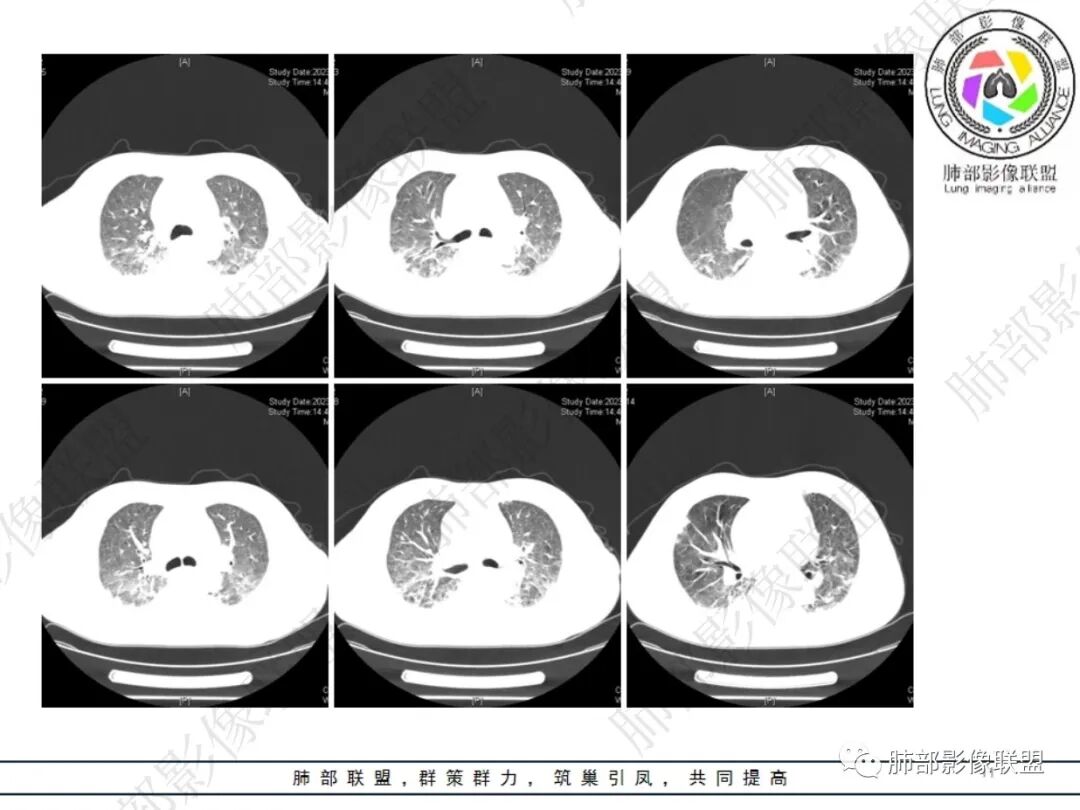

六、影像学表现:

①局限或弥漫肺部浸润影,可为GGO、斑片影、大部分以实变为主。

②单个或多个结节、团块影,结节大小不等,可见粟粒性结节。大部分为较大结节,易形成空洞。

③空洞:较为常见。

④累及胸膜,出现胸腔积液。